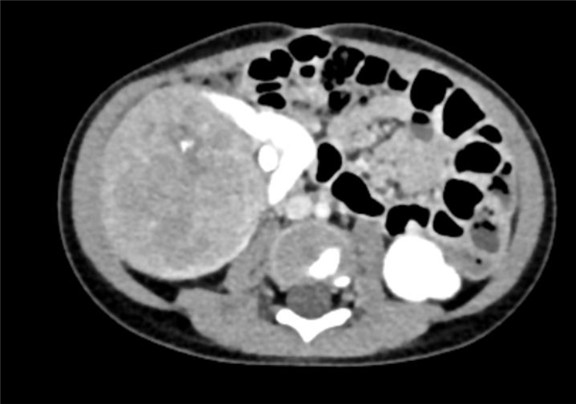

下腹部CT动态增强扫描 肾母细胞瘤化疗后,右肾巨大占位,较前范围减小,请结合临床。

术前CT检查:

动脉期

静脉期

平衡期